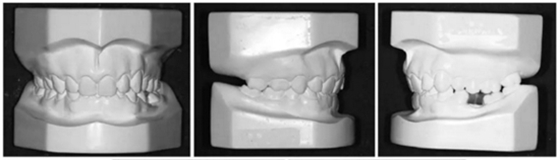

3.體格檢查:直面型,露齦笑,深覆合、合平面傾斜(Figure 1)。上中線偏右3mm,下中線偏左2mm。磨牙II類關(guān)系,左側(cè)尖牙II類關(guān)系,右側(cè)尖牙I類關(guān)系,左下第二磨牙低位咬合,右上前磨牙缺失。覆蓋率為100%,覆蓋度為4mm。咬合平面重度傾斜,左側(cè)向下移位(Figure 2、3)。